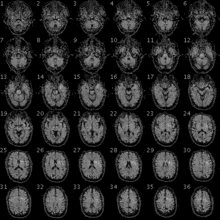

FMRI image of the brain of a participant in the Personal Genome Project.

Despite these difficulties, fMRI has been used clinically to map functional areas, check left-right hemispherical asymmetry in language and memory regions, check the neural correlates of a seizure, study how the brain recovers partially from a stroke, test how well a drug or behavioral therapy works, detect the onset of Alzheimer's, and note the presence of disorders like depression. Mapping of functional areas and understanding lateralization of language and memory help surgeons avoid removing critical brain regions when they have to operate and remove brain tissue. This is of particular importance in removing tumors and in patients who have intractable temporal lobe epilepsy. Lesioning tumors requires pre-surgical planning to ensure no functionally useful tissue is removed needlessly. Recovered depressed patients have shown altered fMRI activity in the cerebellum, and this may indicate a tendency to relapse. Pharmacological fMRI, assaying brain activity after drugs are administered, can be used to check how much a drug penetrates the blood–brain barrier and dose vs effect information of the medication.[46]